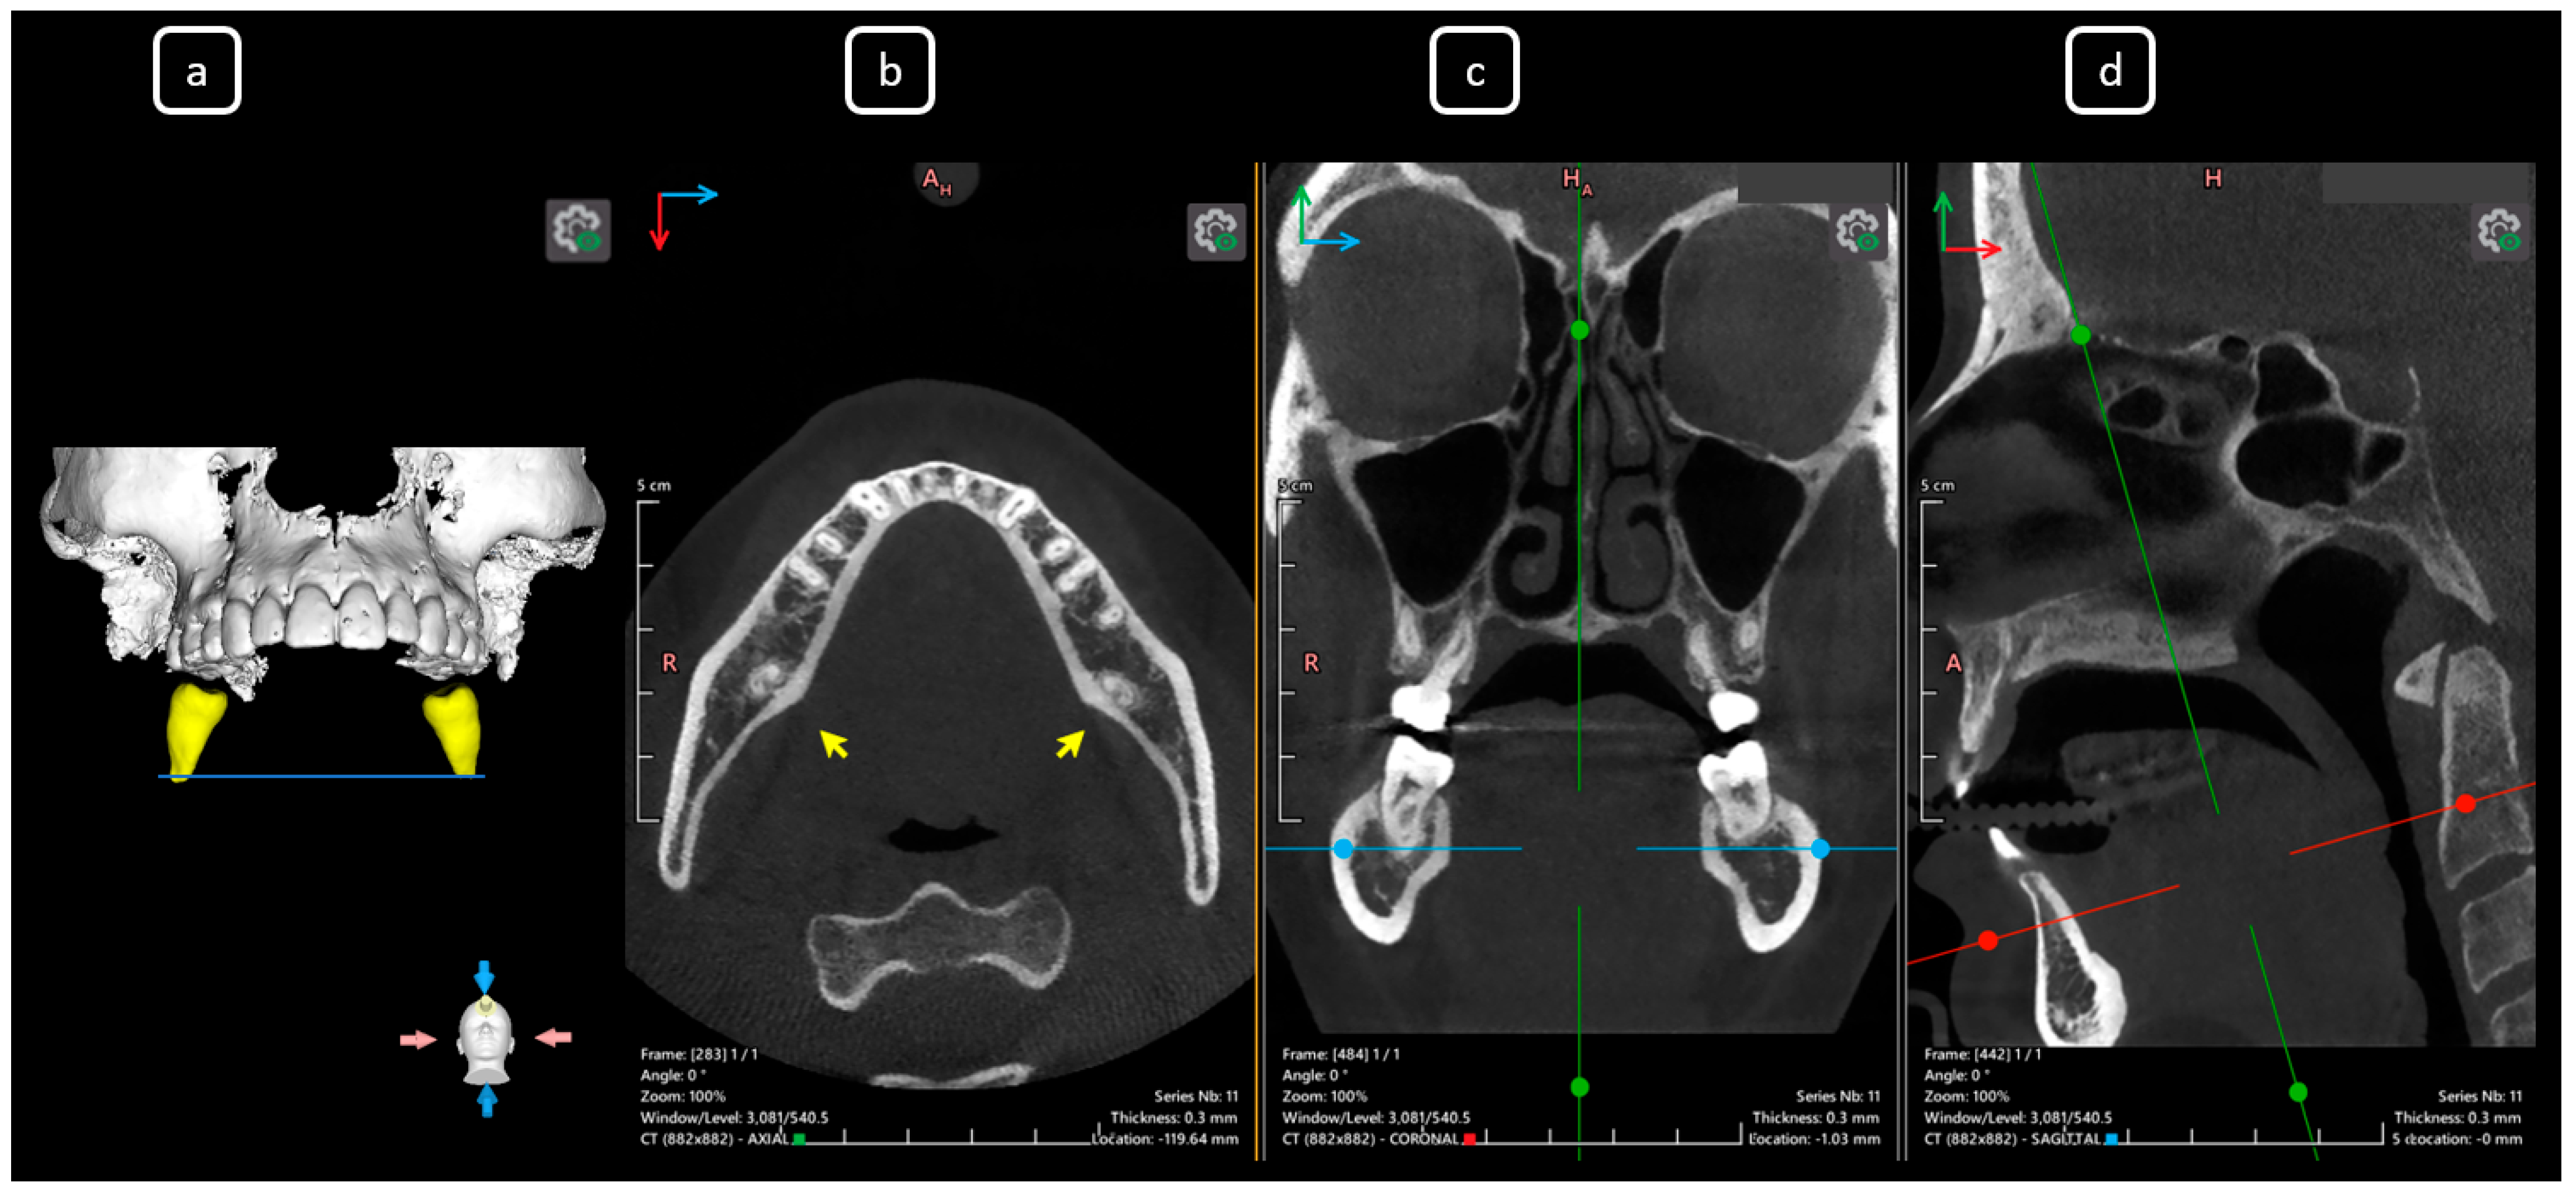

Imaging Findings of Clinical Significance in Endodontics During Cone Beam Computed Tomography Scanning of the Upper Airway—The Anterior, Bilateral, C-Shaped, Dual of Mandibular Root Canals: A Brief Case Report

García-Torres, E.; Guerrero-Falcón, D.L.G.; Bojórquez-Armenta, H.A.; Almeda-Ojeda, O.E.; Barajas-Pérez, V.H.; Solís-Martínez, L.J. Imaging Findings of Clinical Significance in Endodontics During Cone Beam Computed Tomography Scanning of the Upper Airway—The Anterior, Bilateral, C-Shaped, Dual of Mandibular Root Canals: A Brief Case Report. Diagnostics 2025, 15, 3157. https://doi.org/10.3390/diagnostics15243157